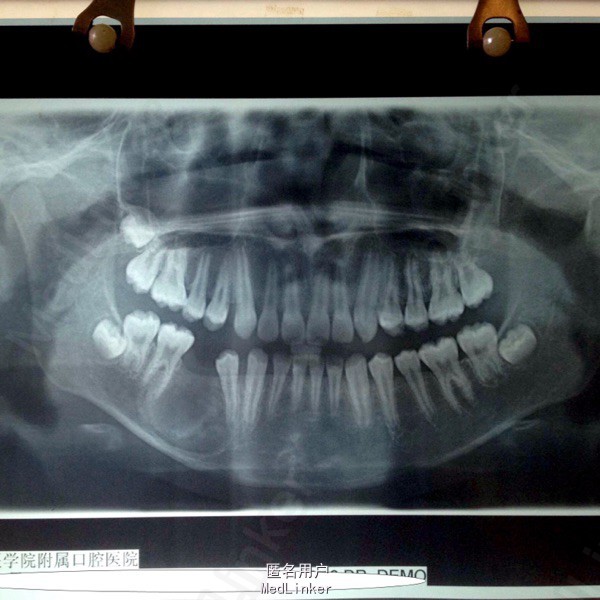

偶然发现右下颌骨包块2月 患者男,11岁,2月前发现右下颌骨区包块,于当地医院就诊,未明确诊断,建议上级医院就诊,遂入我院。

颌面部不对称,口内见右侧下颌颊侧膨隆,大小约3cm*4cm,质硬,不活动,无压痛。黏膜正常。85龋坏,滞留。44-46根尖低密度影,周围高密度致密影,45埋伏阻生。

右下颌骨含牙囊肿 局部开窗引流术,拔除滞留乳牙及埋伏阻生牙。同期取少量标本病检。

术后病检提示含牙囊肿。随访提示局部病变区囊肿缩小,新骨形成。目前仍处于随访阶段,并拟安排后续正畸治疗。 讨论:颌骨囊肿治疗方式非常多,传统填塞碘仿纱条,植骨(粉),引流~考虑患者年龄,后续治疗不适合做种植手术,植骨对正畸治疗有一定影响。综合考虑选择引流法,也取得了预期效果。但囊肿有向成釉细胞瘤转化可能,需术前告知患方,并坚持随访。